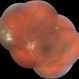

- Toxoplasmosis Active with Vitritis

- toxoplasmosis chorioretinitis, toxoplasmosis uveitis

- Active Toxo